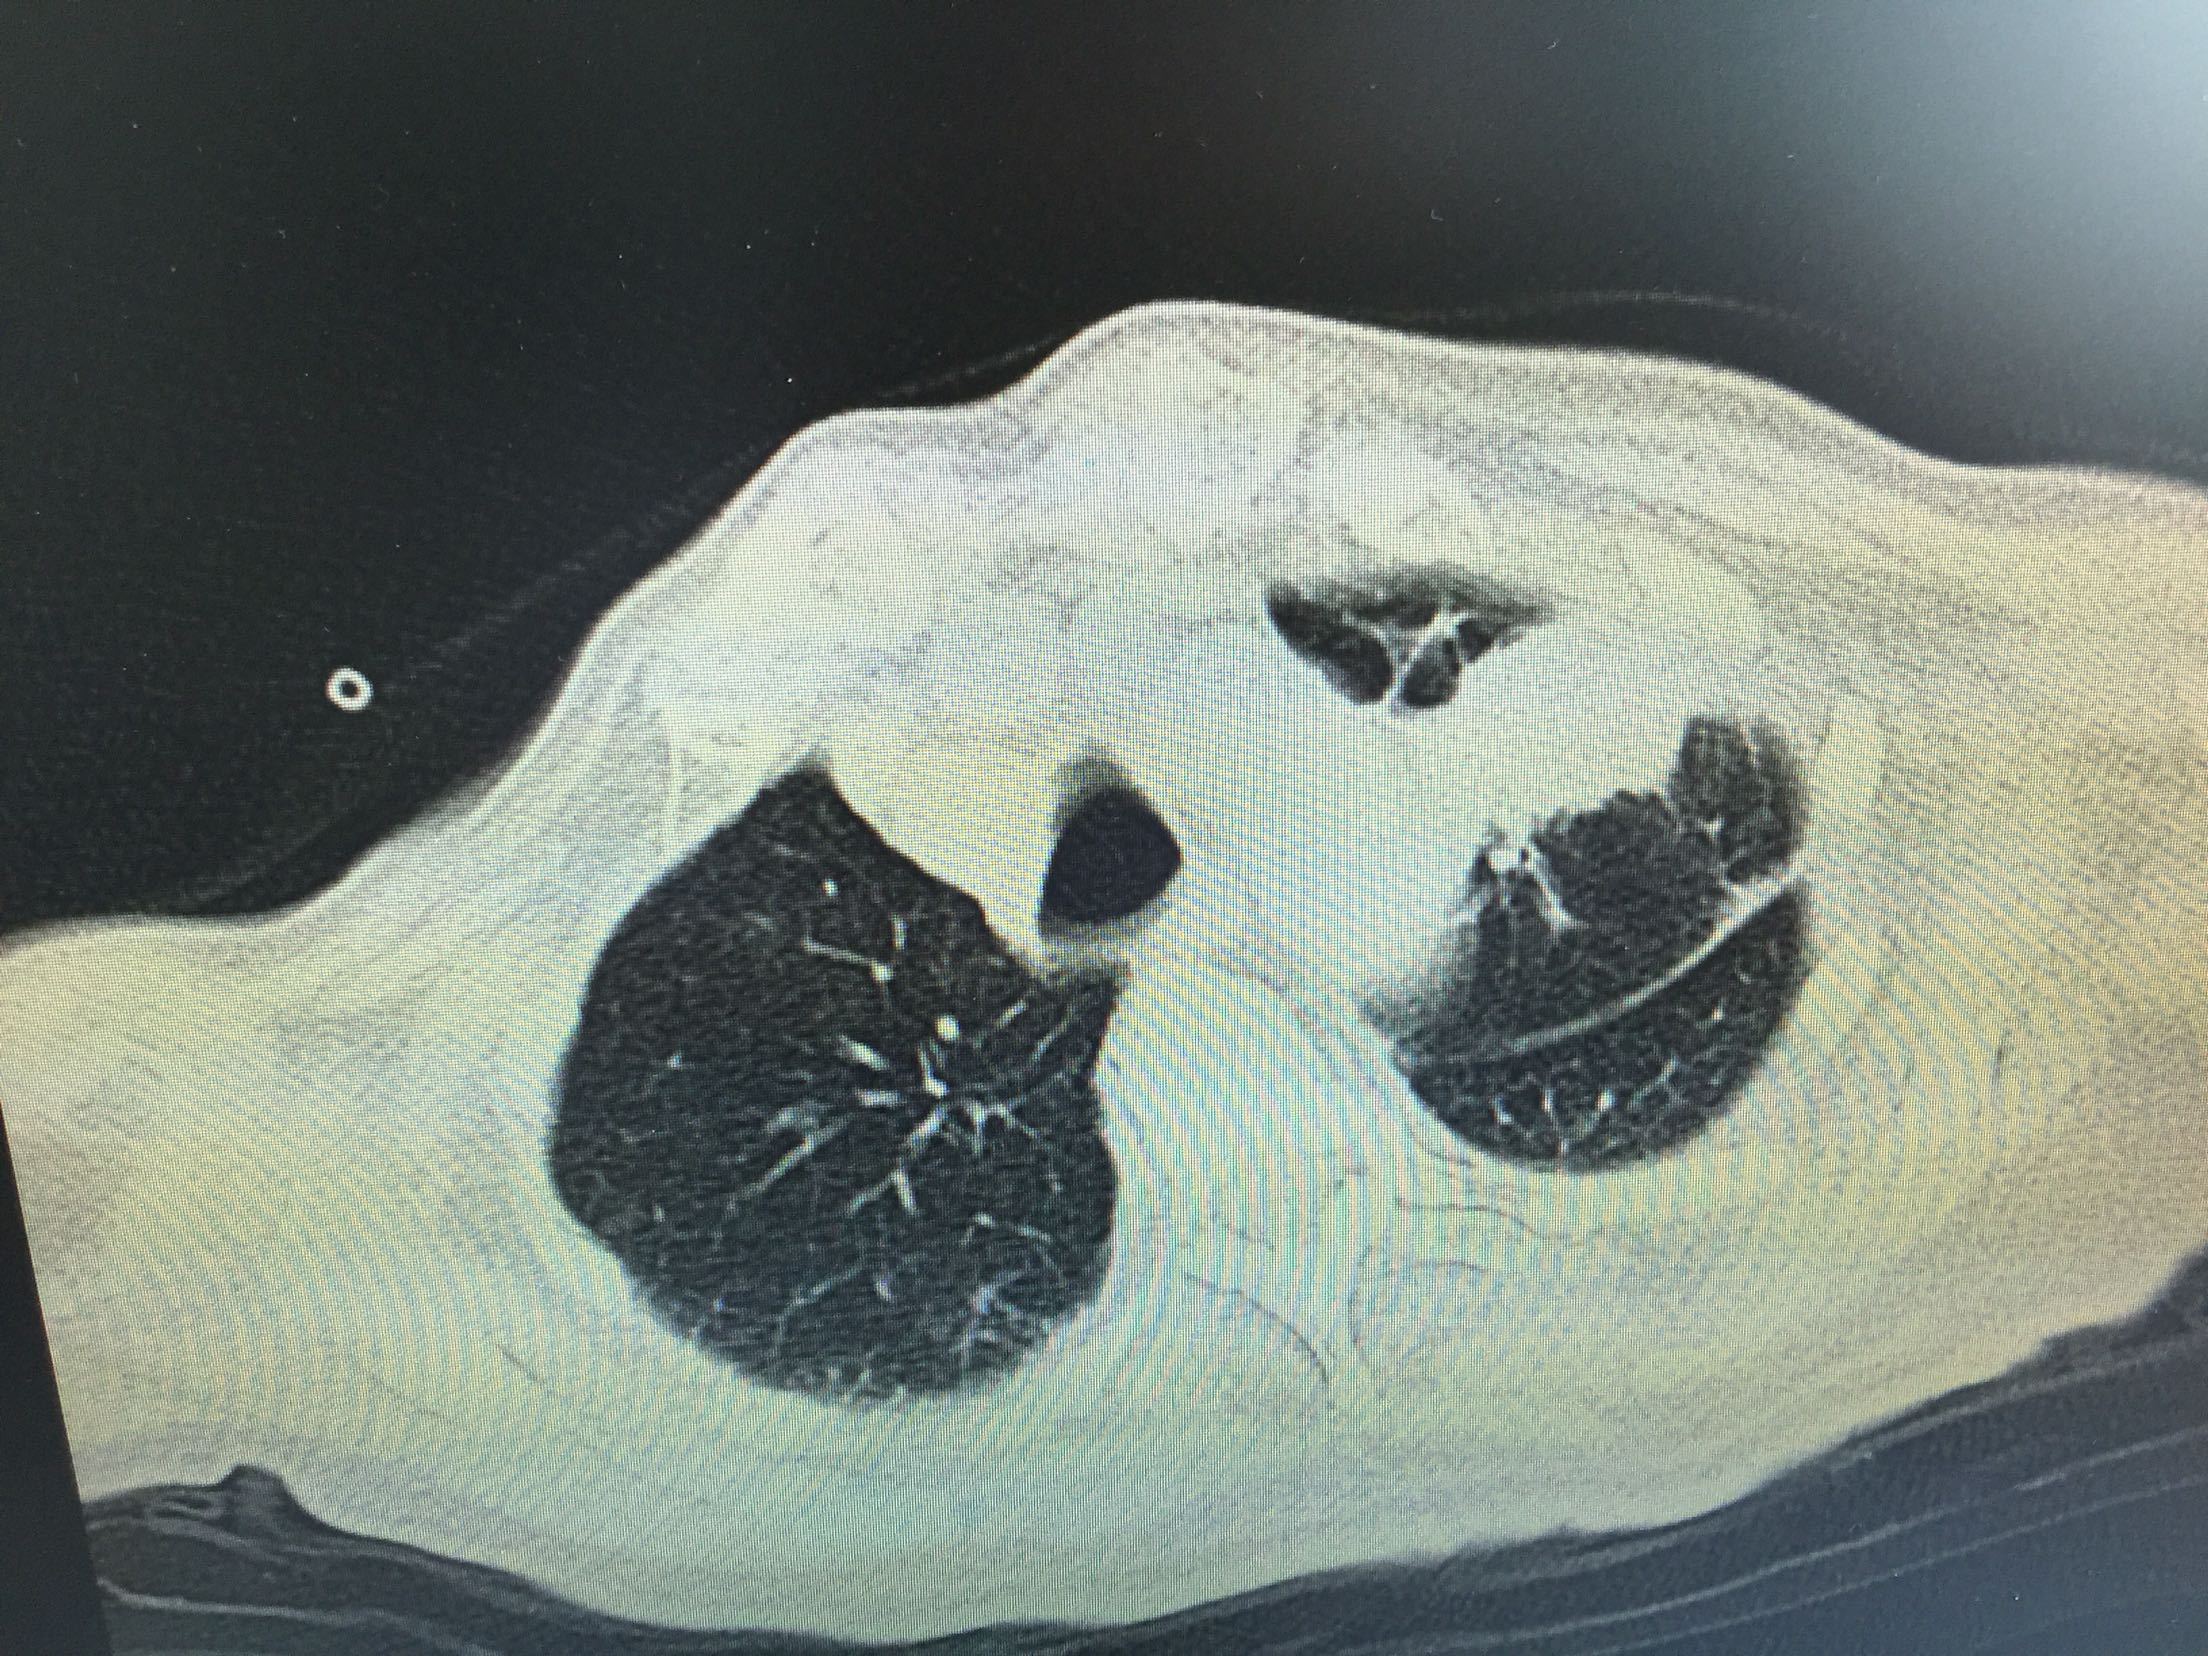

肺癌脑转移1例。

女,81岁,以“意识障碍1天”入院。

1.肺癌脑转移。 治疗:营养神经、脱水、抗感染、化痰、维持离子平衡治疗。